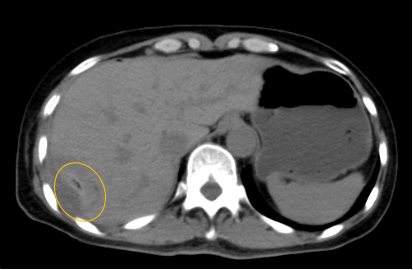

入院后,影像診療中心立即給李女士完善了CT和MR檢查,發(fā)現(xiàn)病變位于肝包膜下,臨近膈肌,消融治療過程中有并發(fā)損傷膈肌的可能,難度較大,但是采用精準(zhǔn)影像定位是可以完成的。陳寶瑩主任立即與腫瘤三病區(qū)劉金鵬主任聯(lián)系,并與影像微創(chuàng)治療小組進(jìn)行MDT討論:患者為卵巢癌肝右葉包膜下單發(fā)轉(zhuǎn)移瘤,最長(zhǎng)徑不超過3cm,患者對(duì)局部治療的主觀愿望強(qiáng)烈,符合消融治療專家共識(shí),遂制定了影像引導(dǎo)下局部消融治療聯(lián)合全身治療的綜合治療方案。

針對(duì)這個(gè)特殊部位的腫瘤,要想消融完全,那么膈肌損傷的風(fēng)險(xiǎn)就很高,陳寶瑩主任帶領(lǐng)影像微創(chuàng)亞專業(yè)組成員仔細(xì)閱讀CT圖像,設(shè)計(jì)進(jìn)針路徑,結(jié)合MR圖像確定腫瘤活性范圍,制定了周密而詳盡的消融計(jì)劃。臘月二十九,即住院第二天影像微創(chuàng)治療小組圓滿為患者完成了腫瘤微波消融治療,觀察24小時(shí)后出院回家過年。術(shù)后48小時(shí)隨訪患者無(wú)明顯不適,術(shù)后7天隨訪,患者肝功、血常規(guī)等各項(xiàng)指標(biāo)均恢復(fù)正常。